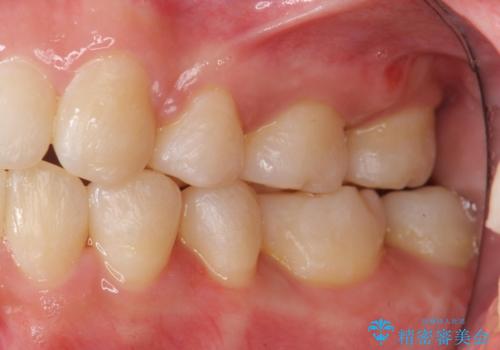

前歯は重度のがたつき、また奥歯はすれ違っていました。

治療は3年以上かかりそうと説明しましたが、2年台で終わらせることができました。

上下左右4本抜歯の可能性を説明していましたが、実際は上顎2本の小臼歯抜歯で済みました。

矯正用インプラントを使用して治療しています。

上下の顎の幅もあっておらず、成人でしたが手術なしで上あごを骨から広げる処置(急速拡大装置)を行いました。